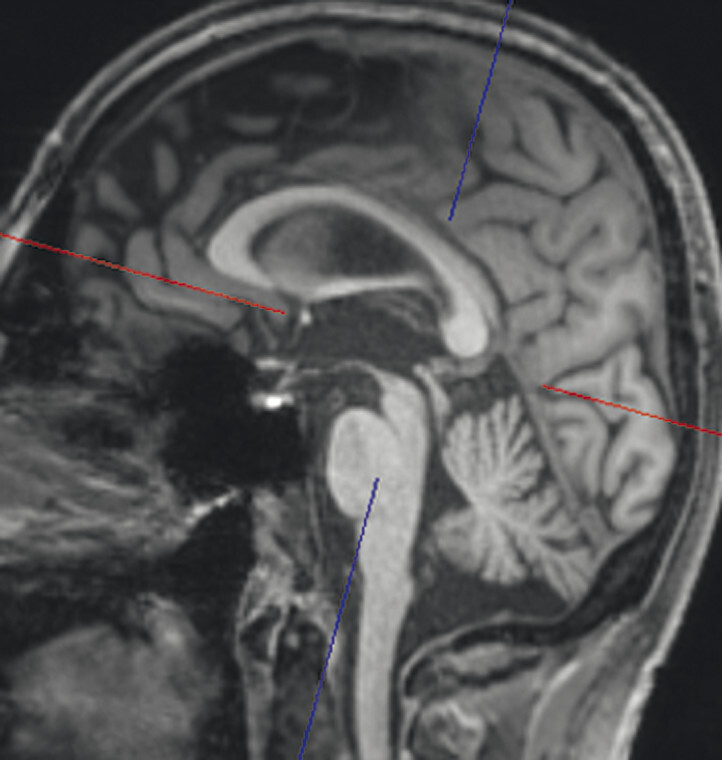

Abb. 69.4 Parkinson-Syndrome: Differenzialdiagnose Normaldruckhydrozephalus.

Typische Aspekte im MRT. Das DESH-Zeichen (a, Pfeile) ist am zuverlässigsten in Bezug auf das Erkennen des typischen Erscheinungsbilds eines Normaldruckhydrozephalus (a, b). Um ein weiteres typisches Zeichen, den spitzen Corpus-callosum-Winkel, verlässlich bestimmen zu können, ist es wichtig, den T1w 3-D-Datensatz exakt in der Commissura-anterior-Commissura-posterior-Linie zu orientieren (d, Pfeile) und den Winkel der Corpus-callosum-Schenkel in der koronaren Ebene auf Niveau der Commissura posterior (d, blaue Linie) zu bestimmen. Ein Corpus-callosum-Winkel von weniger als 90° gilt als anomal und als Hinweis auf den Aspekt eines Normaldruckhydrozephalus (e).

a DESH-Zeichen: disproportionale Erweiterung der inneren Liquorräume und der Sylvi-Fissur (Pfeile).

b DESH-Zeichen: enggestellte frontoparietale Liquorräume der Konvexität (s. auch a).

c Bei fortgeschrittenem Normaldruckhydrozephalus kommt es zusätzlich zu einer Liquordiapedese über die Ventrikelwände in das periventrikuläre Marklager, speziell im Bereich der Seitenventrikelvorder- und -hinterhörner (Polkappen).

d Spitzer Corpus-callosum-Winkel: Orientierung des T1w 3-D-Datensatzes exakt in der Commissura-anterior-Commissura-posterior-Linie (blaue Linie) und Bestimmung des Winkels der Corpus-callosum-Schenkel in der koronaren Ebene auf Niveau der Commissura posterior.

e Spitzer Corpus-callosum-Winkel: Beispiel eines pathologischen Corpus-callosum-Winkels.